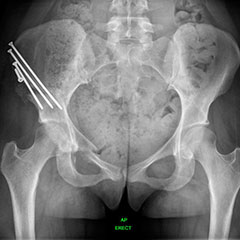

DDH (Hip Dysplasia)

Developmental dysplasia of the hip (DDH) is the most common paediatric hip condition. Abnormal hip development in the womb leads to a joint that can be unstable or even dislocated at birth. Children may present with a leg length discrepancy, restricted abduction, abnormal gait (walking) or even signs of instability. This can be missed, especially if both sides are affected. Earlier treatment is less invasive and more effective.

Dysplastic hips on child - before

Dysplastic hips on child - after

Hip preservation - before

Hip preservation - after